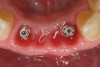

Figure 4  Tapered implants with conical transgingival abutments and temporary cylinders in place.

Figure 4

Preoperatively, 1 g of amoxicillin was administered. Using local anesthesia (lidocaine 1:100,000 epinephrine), extractions of teeth No. 23 to No. 26 were performed without raising a flap and with gentle luxation to preserve the remaining facial osseous plate. The sockets were curetted prior to implant placement. A vacuum-formed surgical guide, fabricated based on a diagnostic wax-up of the desired tooth positions for the subsequent fixed prosthesis, was used during implant placement. Osteotomies were performed at sites No. 23 and No. 26 and positioned toward the lingual aspects of the sockets (Figure 3A and Figure 3B). Two tapered implants (OsseoTite™ 313, BIOMET 3i™, Palm Beach Gardens, FL) measuring 3.25 mm x 13 mm were placed. Conical prosthetic abutments (3-mm height) were used to facilitate joining the two implants in a screw-retained fixed partial denture (Figure 4). A laboratory-processed acrylic-resin provisional restoration was altered to allow connection to the temporary cylinders. The provisional was placed into the vacuum-formed surgical guide that was now used to maintain the provisional in the correct 3-dimensional position (Figure 5) while being attached to the temporary cylinders with acrylic resin intraorally. Once a sufficient amount of acrylic resin was placed to secure the cylinders to the provisional, it was removed from the mouth and its contours were completed at the laboratory bench (Figure 6A). The two central incisor sockets were grafted with small-particle allograft material (Puros® Allograft, Zimmer Dental, Carlsbad, CA) to maintain gingival architecture beneath two ovate pontics (Figure 6B). The provisional restoration was inserted and the screws tightened to 20 Nt-cm of torque.